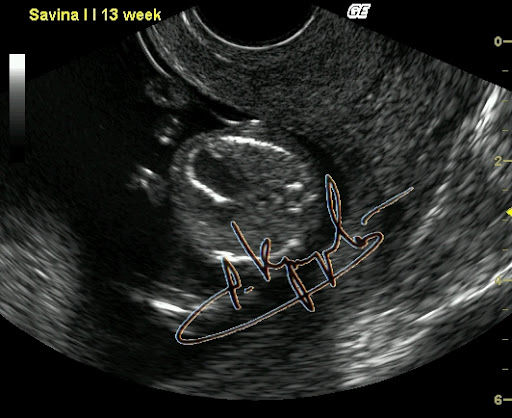

Фиброэластоз эндокарда. Диагностика на ранних сроках возможна.

Вот как быть? Вроде обещал нескольким человечкам рассказать про внутриутробный фак, но совершенно не уверен что получится что-то путнее. Хотя чем черт не шутит. Попробую. Было это буквально на днях, в четверг. Но лучше издалека начать. С именем Настя у меня по жизни непременно связан какой-то налёт чудесатости. Ну есть что-то такое... Что-то буквально на кончике не пойми чего. Как модно говорить "флёр @панутости". То, что даже издалека отличает любую Настю от носительниц других имен. Или, перефразируя вышесказанное, - нормальных Насть я в своей жизни пока не встречал. Это в качестве предисловия, хотя некоторые и осуждают любые эпиграфы. А кто сказал эпиграф? Я сказал - предисловие. Чуете разницу? Нет? Дело ваше. Полумрак кабинета. Беременность 24 недели. И Ваш покорный слуга, мучающий подслеповатые (уже весьма-весьма, увы) глаза перед экраном, согнувшись над животиком. УЗИ делаю. Сердце плода исследую (эхокардиография называется). Когда-то давно я эту методику отработал до совершенства. Ну то да сё, кровоток через клапаны, время изгнания, время релаксации и прочая хитромудрая мутотень. Тут Настя и говорит: - Ну что, показывает? Кто там у нас? (Настя - это беременная) - Какой пол? А разве не говорил на прошлом УЗИ? - Нет, не было видно. Ну это часто бывает. Вот втемяшится что-то ребятенку в животике и так упрется рогом в плаценту, то можно и до самых родов не узнать. Вот всеми возможными способами будет прятаться. То руками закрывать, то пуповину наматывать, то ноги сжимать. Ну бывает, поэтому особо не придал значения. Сердце закончил обследовать, - все нормально. И слава Богу. - Хорошо, говорю, - сейчас посмотрим кто-там прячется. Начал пытаться разглядывать. И так и сяк, короче и руку себе вывернул и глаза сломал. Потом на пару секунд плод ноги разжал и рукой, которой свою письку прикрывал, показал мне... натуральный фак. Секунды три подержал средний палец мне перед глазами и опять руки в промежность и ноги сжал. Я не выдержал и расхохотался. Мамашке говорю: - никогда мне еще за 25 лет с экрана плоды фак не показывали. Тут уже мамашка в хохот. Я весь в непонятках. А она мне: - Доктор, так в прошлый раз Вы тоже рассмотреть не могли, я три раза на кушетку ложилась и вставала. Но в тот раз ребенок вам... козу показывал. И правда. Вспомнил таки эту Настю. Кинулся искать в базе данных. И действительно - так и записано: Бурум-бурум Анастасия Паповна, Бер 18-19 нед, КЗ, ХЗ(показывала козу). И вот если бы мне кто рассказал, я бы не поверил. И главное - это оказалась девочка!!! Представляете, что за хулиганка растет? Кстати, у этой истории еще и продолжение есть. Но не сегодня.